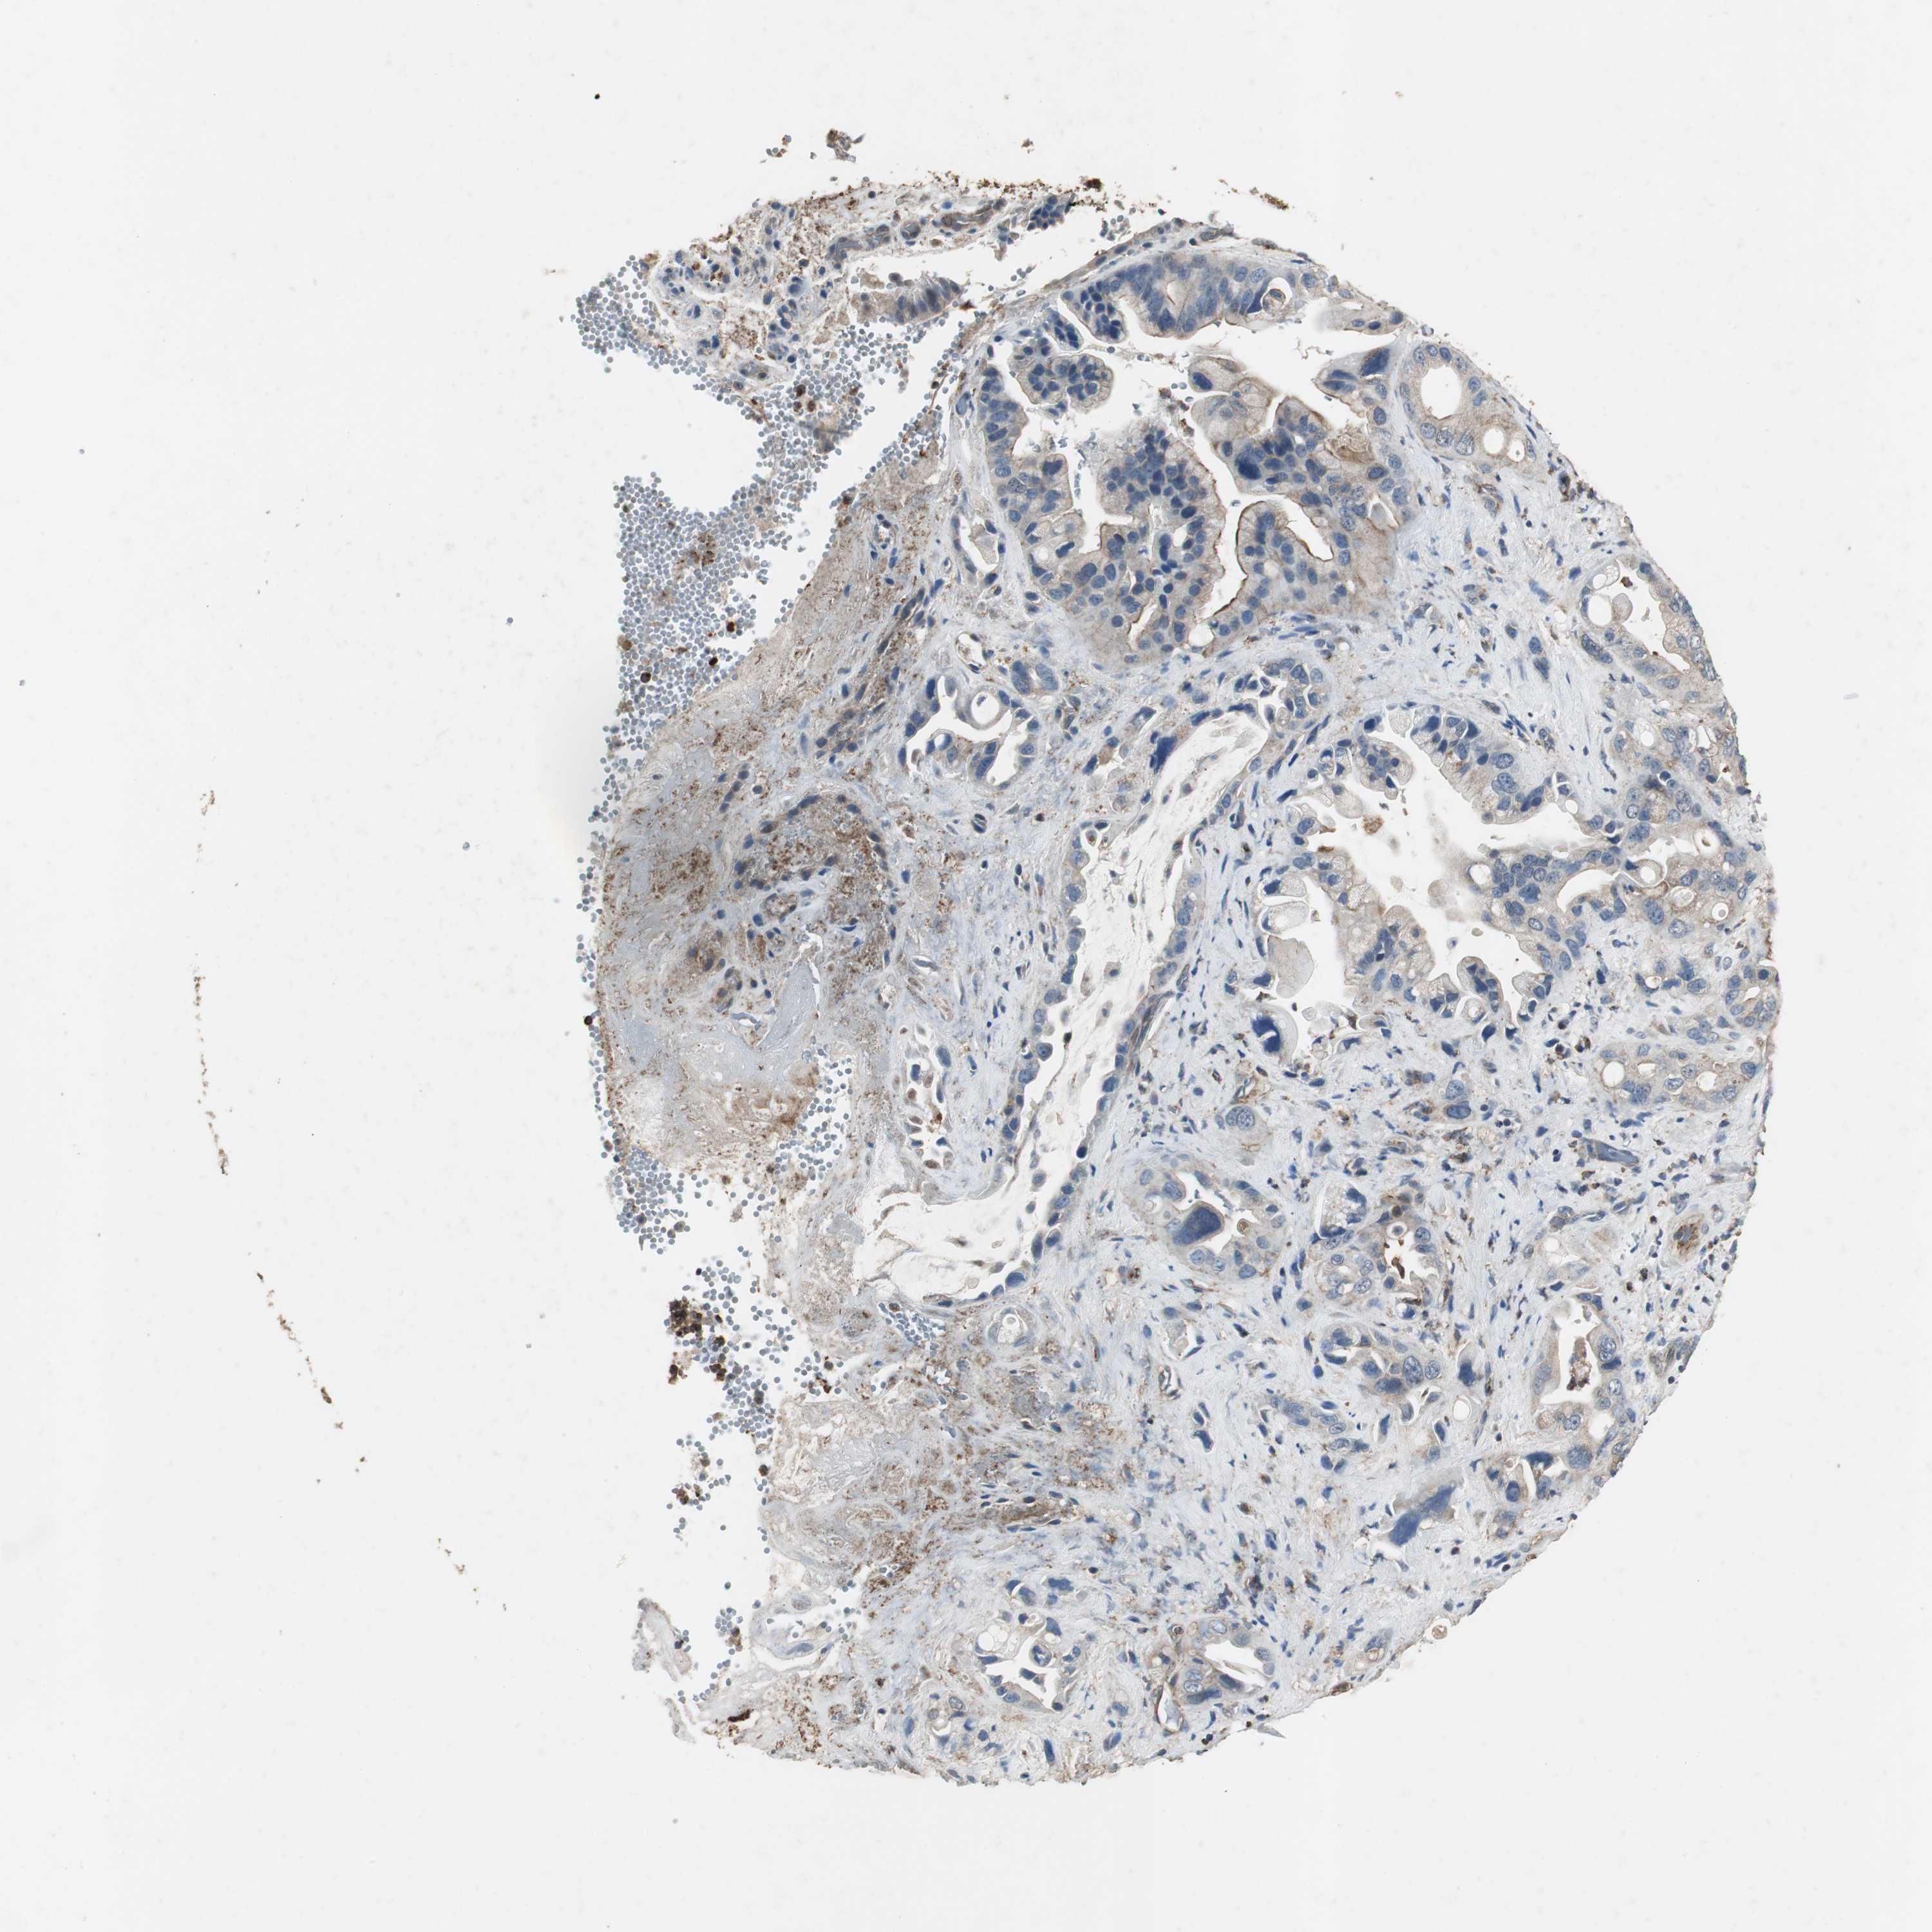

PANCREATIC CANCER - Protein expressioni

A mouse-over function shows sample information and annotation data. Click on an image to view it in a full screen mode. Samples can be filtered based on level of antibody staining by selecting one or several of the following categories: high, medium, low and not detected. The assay and annotation is described here.

Note that samples used for immunohistochemistry by the Human Protein Atlas do not correspond to samples in the TCGA dataset.

Antibody stainingi

Antibody staining in the annotated cell types in the current human tissue is reported as not detected, low, medium, or high, based on conventional immunohistochemistry profiling in selected tissues. This score is based on the combination of the staining intensity and fraction of stained cells.

Each image is clickable and will lead to virtual microscopy that enables deeper exploration of all samples and also displays staining intensity scores, fraction scores and subcellular localization as well as patient and tissue information for each sample.

Antibody HPA006514

Staining

High

Medium

Low

Not detected

Intensity

Strong

Moderate

Weak

Negative

Quantity

>75%

75%-25%

<25%

None

Location

Nuclear

Cytoplasmic/membranous

Cytoplasmic/membranous,nuclear

Adenocarcinoma, NOS

Adenocarcinoma, metastatic, NOS